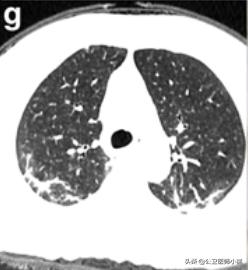

中心结节周围毛玻璃样改变

中心结节、周围毛玻璃样改变